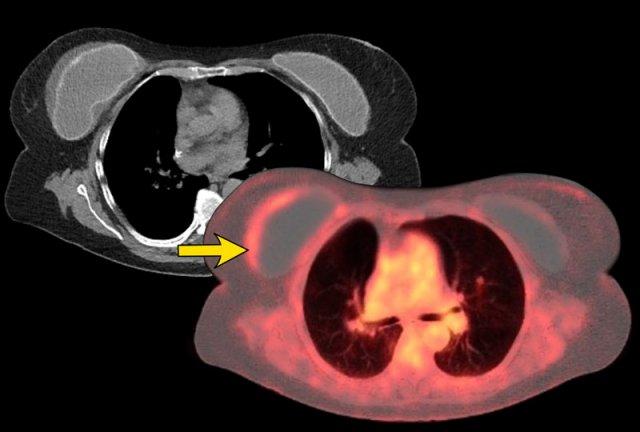

Hai phần ba bệnh nhân BIA-ALCL biểu hiện bằng triệu chứng khó chịu và sưng nề do sự hình thành tràn dịch quanh túi ngực (85%), trong đó phát hiện các tế bào lympho không điển hình. Đôi khi có kèm theo khối u trong 15% trường hợp.

Bất kỳ trường hợp tràn dịch hoặc khối u một bên xuất hiện muộn nào cũng cần được chọc hút và phân tích tế bào học.

Phân giai đoạn bệnh được thực hiện bằng PET-CT, tương tự như các loại u lympho khác.

Phần lớn bệnh nhân được chẩn đoán ở Giai đoạn 1.

Phương pháp điều trị là phẫu thuật cắt bỏ túi ngực, bao xơ và khối u (nếu có).

Tiên lượng thuận lợi khi được điều trị sớm.